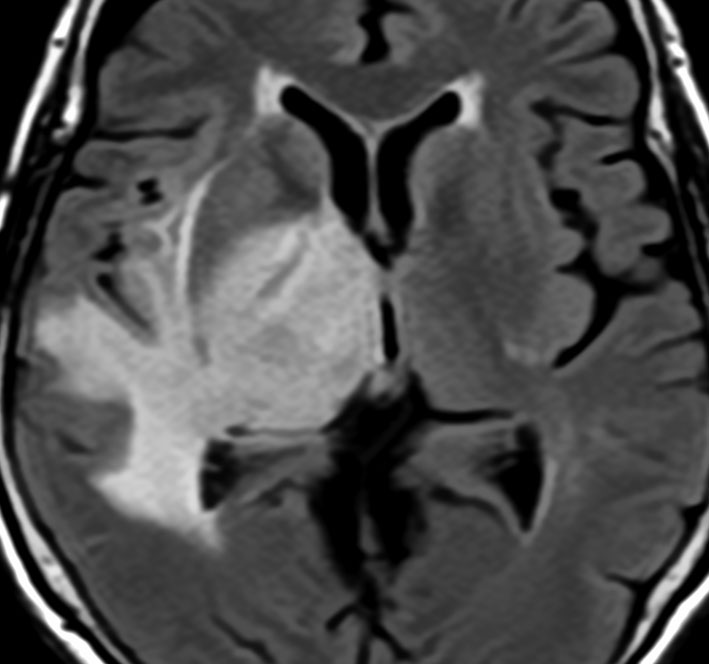

右側頭葉島の病変です。1年間の経過ではっきり増大したので,無症状でしたが生検術を行いました。病理組織では,異型グリアの増殖はありましたが,核分裂蔵,血管内皮の増生や壊死は明らかではありませんでした。しかし,遺伝子診断ではIDH1/2 野生型,ATRX retained,TERT promotor野生型,1p/19q共欠失なしでした。膠芽腫という確定病理診断です。

標準治療を加えましたが,数ヶ月後に急激な増大を呈しました。グレード4の臨床像です。MRI画像よりも病理組織像よりも,遺伝子診断の方がより性格に予後を示す例です。